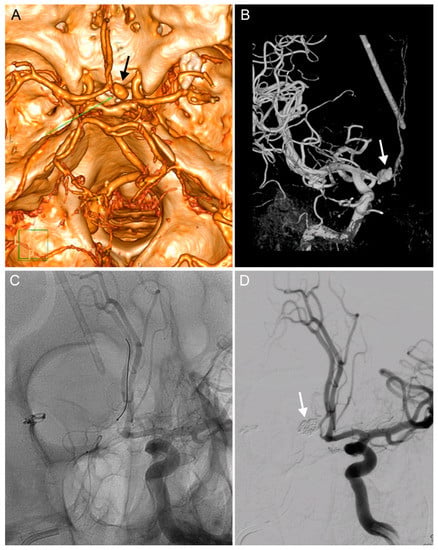

We decided to treat the pathologies immediately, which necessitated the insertion of a caval filter due to deep vein thrombosis. The following day, a ventriculo-peritoneal shunt (Certas, Medtronic) was implanted and, six days later, diagnostic angiography was performed and verified the presence of a 17 mm PSA in the distal A1 segment of the ACA (Figure 2A,B). The PSA was coiled the following day (Cosmos Complex spirals into the aneurysm dome, Target Nano in the aneurysm ostium and the A1 segment of the ACA). The patency of the ipsilateral A2-3 via the anterior communicating artery was verified in the final angiogram, which also demonstrated complete occlusion of the PSA (Figure 2C,D). No further neurological deficits developed following the endovascular procedure and the patient was successfully treated for suspected shunt meningitis (negative bacterial cultures) with meropenem. The patient was transferred to his local hospital and later released.

Figure 2.

Diagnosis and endovascular treatment of an iatrogenic PSA of the A1 segment of the right anterior cerebral artery (ACA). (A). CT angiography showing a PSA of the right A1 segment (arrow). (B). The same PSA on a diagnostic digital substraction angiography (DSA, arrow) after implanting a ventriculo-peritoneal (VP) shunt. (C). An endovascular intervention for the PSA: a guidewire in the right ACA. (D). Angiography showing completed coiling of the PSA and showing patency of both A2 segments.